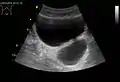

Diverticulum of the urinary bladder of a 59-year-old man, transverse plane

Bladder diverticula containing stones: the bladder wall is thickened due to possible transitional cell carcinoma.- Bladder diverticula as seen on ultrasound with doppler[18]

- Bladder diverticula as seen on ultrasound[18]